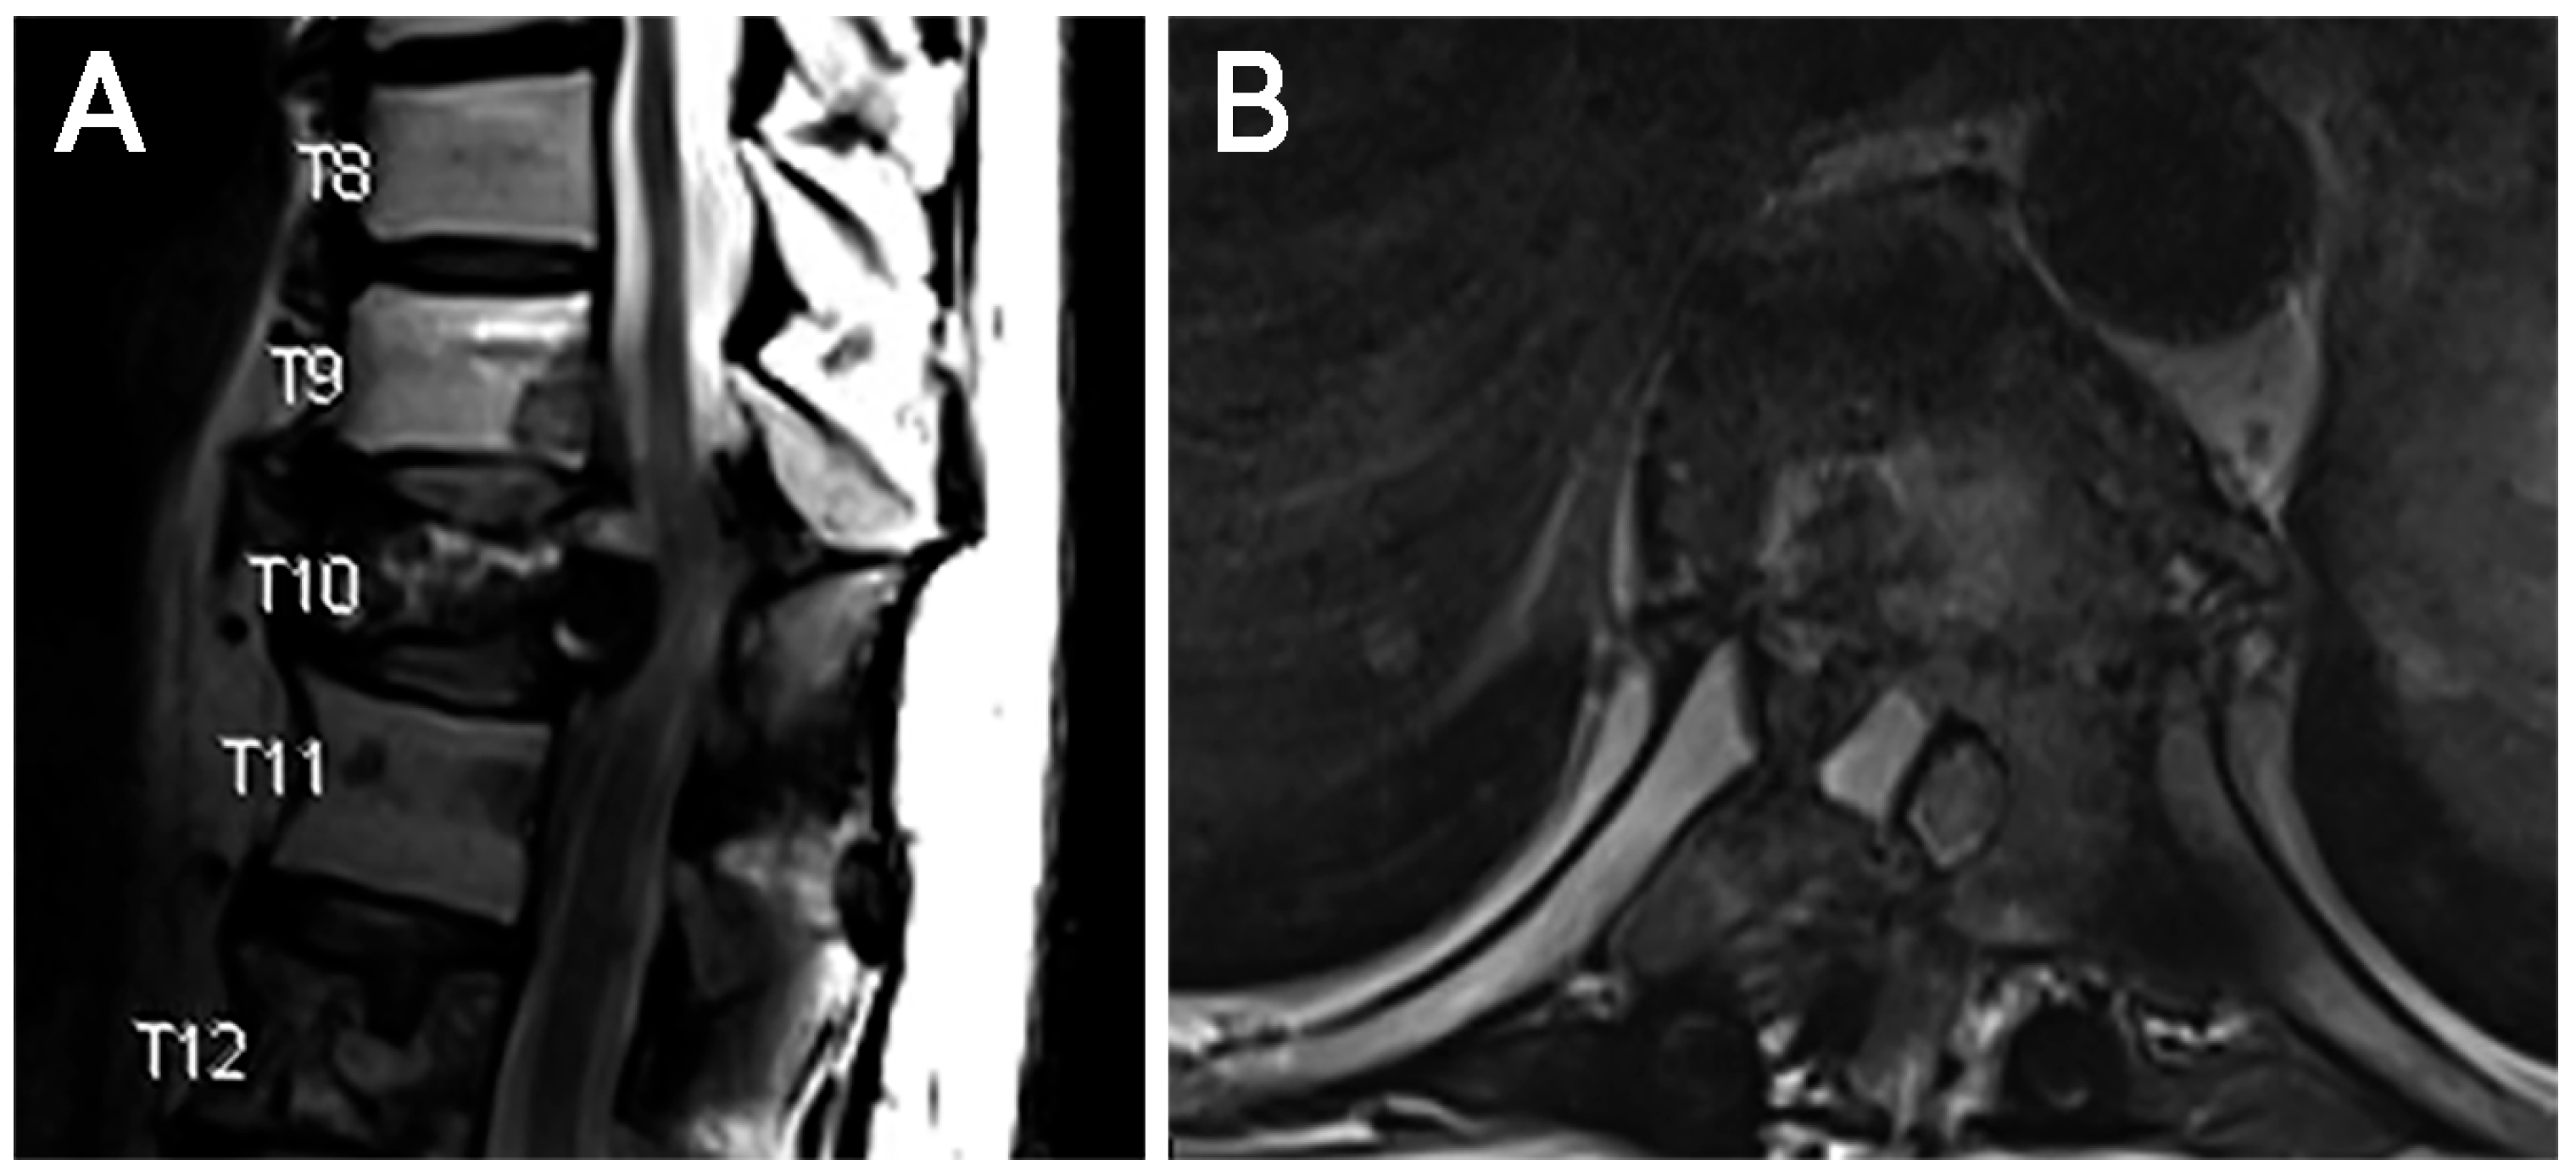

The patient presented again in 2025 with worsening lower extremity paresthesias and numbness from his hips to his knees, impeding his ability to walk. Magnetic resonance imaging demonstrated progression of the known T10 lesion with associated canal stenosis (Figure 4). After discussion with radiation oncology, the decision was made to pursue endoscopic separation surgery via a transpedicular approach to facilitate SBRT.

Figure 4. Case 2. Preoperative imaging. (A) T2 sagittal and (B) axial imaging demonstrating T10 metastatic lesion with associated canal stenosis.